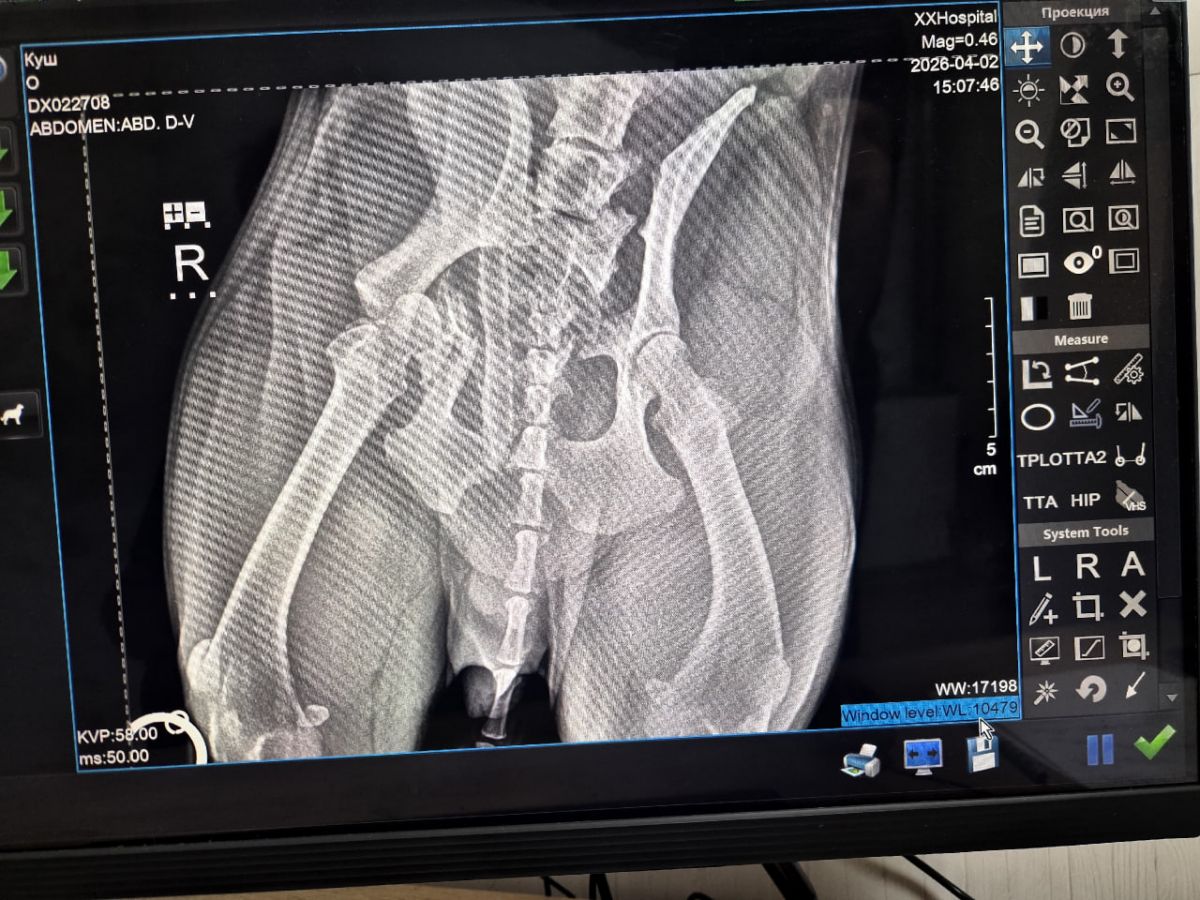

После обследования ветеринары поставили диагноз: перелом подвздошно-крестцового сочленения с обеих сторон и перелом вертлужной впадины справа. Для восстановления здоровья питомца требуется дорогостоящая операция – остеосинтез таза и резекционная артропластика.